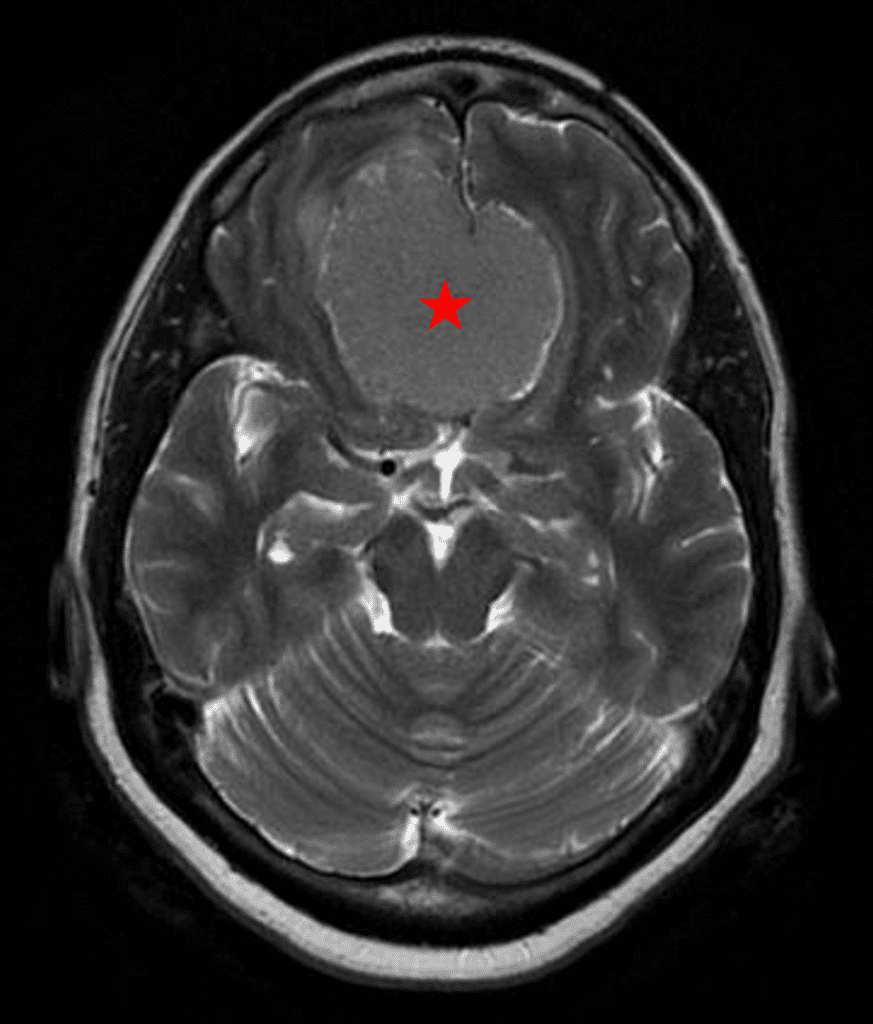

Figure 2b – Postoperative MRI demonstrating resolution of mass effect.

She was started on high-dose steroid and antiseizure prophylactic medicine. Surgical intervention was offered for mass effect, symptomatic relief, neurologic preservation, and histopathologic diagnosis. Dr. Gaudin performed a bifrontal craniotomy with complete resection of neoplasm through an interhemispheric and subfrontal approach. Postoperative imaging demonstrated a gross total resection without residual tumor and resolution of mass effect (Figure 1b and 2b). Intraoperative pathology was consistent with meningioma, WHO grade 1. She recovered very well, and was discharged home on postoperative day 3. On her follow-up outpatient visit, her preoperative symptoms had fully resolved, and her olfactory sense was maintained.